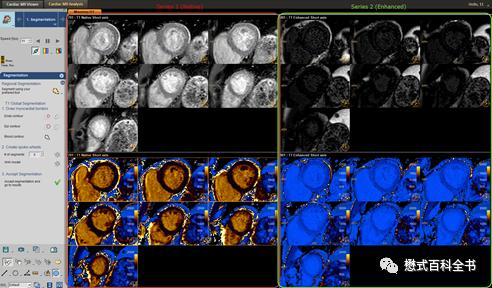

图19、20:工作站处理T1 mapping图

和T2及T2*不同,T1 mapping扫描完仅仅得到T1值不够,我们还需要计算出ECV值和得到ECV mapping。所以,T1 mapping扫描完了还有一个后处理的过程。

一般来说,很多医院是通过购买第三方的工作站来处理一些心脏的高级功能,比如:Medis,CVI等。

当然,很多厂家自带的工作站也能处理很多,比如飞利浦的ISP。后面新版本的ISP工作站是可以直接处理心脏定量图像得到ECV图的。